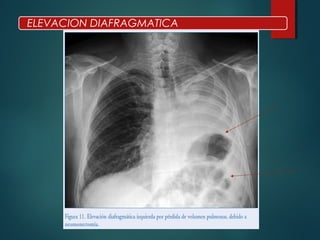

ELEVACION DIAFRAGMATICA

• #42 El líquido se sitúa entre la base pulmonar y el hemidiafragma, simulando un diafragma más elevado. La radiografía PA sugiere este diagnóstico cuando la cúpula parece estar más cercana al ángulo costodiafragmático y después desciende de un modo brusco. La radiografía lateral ayuda en la sospecha diagnóstica y muestra una concavidad posterior, y una radiografía de tórax en decúbito lateral confirma el diagnóstico Parálisis frénica, debido a intervención quirúrgica sobre la zona o por afectación por tumores pulmonares primitivos, mediastínicos o del propio diafragma. La presencia de masa mediastínica y elevación diafragmática debe hacer sospechar la existencia de parálisis frénica. • Patología abdominal. La rotura traumática del diafragma, preferentemente en el lado derecho al permitir que el hígado se hernie, puede simular una elevación diafragmática, así como las masas hepáticas o los abscesos subfrénicos. La herniación o eventración diafragmática puede dar la apariencia de un hemidiafragma elevado.